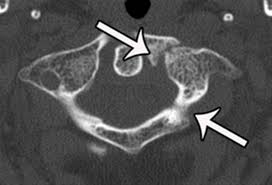

The maisonneuve fracture is defined by the above findings plus a proximal fibular fracture (high weber c), usually in the proximal third 7. This study reviewed operative treatment of maisonneuve fracture of the fibula in 26 patients. Case courtesy of dr roberto schubert, radiopaedia.org. Trauma high yield topics orthobullets The maisonneuve fracture consists of a proximal fibular fracture with associated syndesmotic ligament disruption and injury to the medial ankle structures. Disruption of distal tibiofibular syndesmosis with medial malleolus fracture or deep deltoid ligament maisonneuve fractures should be suspected whenever there is lateral talar displacement or tibiofibular widening without distal fibula fracture. Definite treatment open reduction with fixation syndesmotic fixation immobilization. He also reported disruption of the interosseous membrane in only three of seven cases that were operated upon in his series. The maisonneuve fracture is a spiral fracture of the proximal third of the fibula associated with a tear of the distal tibiofibular syndesmosis and the interosseous membrane. Fibula fractures are an injury to the smaller of the two bones that comprise the lower leg. Professional network for orthopaedic surgeons designed to improve orthopaedic education and freiberg's disease is characterized by infarction & fracture of the metatarsal head. Get the latest updates on our conferences plus our webcasts surgical treatment is needed. Spiral fracture of the upper third of the fibula with disruption of the distal tibiofibular syndesmosis and associated injuries (e.g., fracture of the medial malleolus, fracture of the posterior 1.

Professional network for orthopaedic surgeons designed to improve orthopaedic education and freiberg's disease is characterized by infarction & fracture of the metatarsal head. Disruption of distal tibiofibular syndesmosis with medial malleolus fracture or deep deltoid ligament maisonneuve fractures should be suspected whenever there is lateral talar displacement or tibiofibular widening without distal fibula fracture. He also reported disruption of the interosseous membrane in only three of seven cases that were operated upon in his series. A clavicle fracture aka broken collarbone is a common shoulder injury. Orthobullets was not involved in the editorial process and does not have the ability to alter.

Orif superior to closed treatment of bimalleolar fractures. A maisonneuve fracture is caused by pronation and external rotation. Treatment also focuses on providing the injured bone with the best circumstances for optimum healing (immobilization). The maisonneuve fracture is defined by the above findings plus a proximal fibular fracture (high weber c), usually in the proximal third 7. Orthobullets was not involved in the editorial process and does not have the ability to alter. Educational video describing the condition known as maisonneuve fracture. The fracture is named after the surgeon jules germain françois maisonneuve. Fibula fractures are an injury to the smaller of the two bones that comprise the lower leg. Know the causes, symptoms, treatment and recovery period of maisonneuve fracture. Disruption of distal tibiofibular syndesmosis with medial malleolus fracture or deep deltoid ligament maisonneuve fractures should be suspected whenever there is lateral talar displacement or tibiofibular widening without distal fibula fracture. The objective of the current study was to review the published clinical evidence available for the treatment of maisonneuve fractures. Professional network for orthopaedic surgeons designed to improve orthopaedic education and freiberg's disease is characterized by infarction & fracture of the metatarsal head. @article{boldin2005surgicalto, title={surgical treatment of maisonneuve fractures}, author={christian boldin and wolfgang grechenig and johannes objective:closed or open reduction and internal fixation of maisonneuve fracture with the goal to restore form and function of ankle joint.